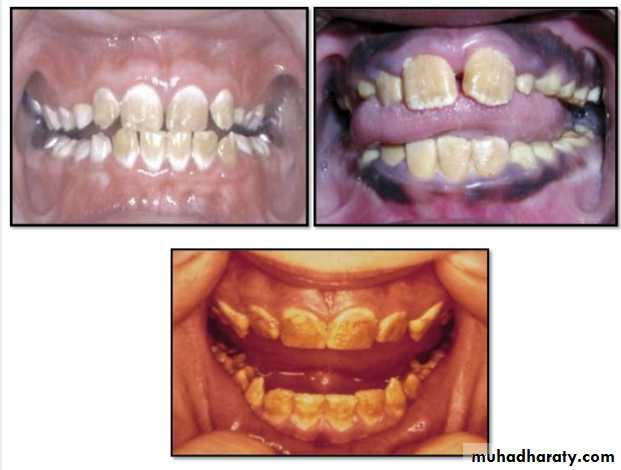

Hypocalcified Amelogenesis Imperfecta:

*Enamel matrix is formed in normal quantity,poorly calcified.

When newly erupted:Enamel is normal in thickness, normal form, but weak , and opaque or chalky in appearance.

With years of function:

Coronal enamel is removed except for cervical portion that is occasionally calcified better.

Radiographically:

Density of enamel & dentin are similar.